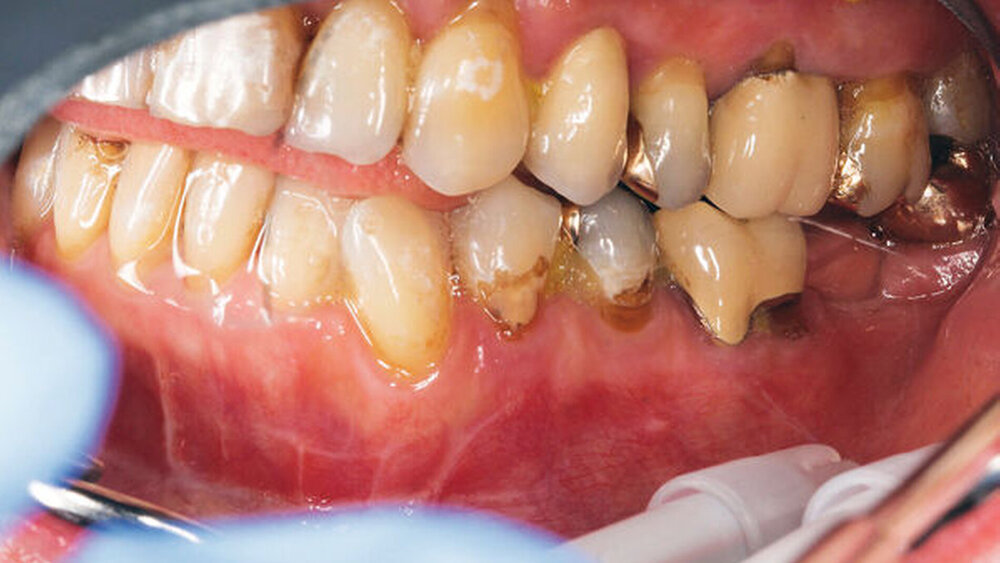

Eine 70-jährige Frau stellte sich auf Überweisung eines niedergelassenen MKG-chirurgischen Kollegen mit einem sich progredient entwickelnden offenen Biss vor. Anamnestisch hatte sie im Urlaub vor drei Monaten einen Fahrradsturz erlitten, war direkt auf das Kinn gefallen und hatte sich dabei eine mehrfragmentäre Unterkieferfraktur (paramedian rechts, Gelenkfortsätze beidseits) zugezogen. Noch am Unfallort erfolgte die offene Reposition und Osteosynthese der Paramedianfraktur. Die beidseitige Collumfraktur wurde geschlossen-konservativ mittels fünfwöchiger intermaxillärer Fixierung behandelt. Klinisch zeigte sich ein frontoffener Biss von circa 4 mm mit Frühkontakt im Molarenbereich (Abbildung 1). Die Patientin konnte auch anhand alter Fotografien überzeugend darstellen, dass dieser vor dem Unfall bei ihr nicht vorgelegen hatte.

Die Patientin war sehr verängstigt, da sich die Situation immer weiter verschlechterte, ihr Biss sich also immer mehr verschob. Insbesondere beklagte sie die kaufunktionelle Einschränkung mit dem Unvermögen des Abbeißens, aber auch den für sie ästhetisch unbefriedigenden Status. Sensorische oder motorische Defizite lagen nicht vor. Eine 3-D-radiologische Untersuchung via dentaler Volumentomografie (DVT) zeigte beidseits in Fehlstellung teilweise pseudarthrotisch eingeheilte Kiefergelenksfortsätze sowie eine suffiziente osteosynthestische Versorgung paramedian rechts (Abbildungen 2 und 3).